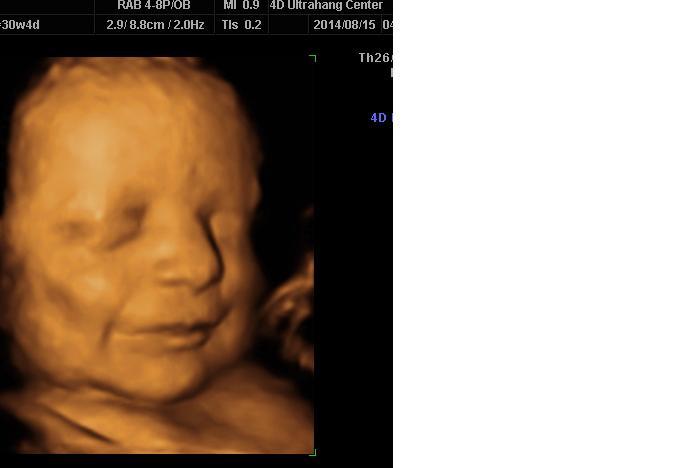

Ádibaba 30.hét :) <3